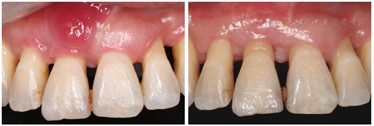

(1)正面观面上1/3比例稍短,面下1/3高度正常;颏部右偏2 mm;上下颌牙齿中线与面中线不一致;上颌中线右偏3 mm;下颌中线右偏2 mm;侧貌突;双侧颞下颌关节区无压痛及弹响,开口度及开口型未见异常;11、21根尖区瘘管;右侧尖牙、磨牙关系远中关系,左侧尖牙、磨牙远中关系;覆盖Ⅲ°,覆合Ⅰ°;上前牙牙轴均向右侧倾斜,15、16联冠,上颌间隙6 mm,37牙列缺失,下颌拥挤度3.5 mm(图1,图2)。(2)牙周会诊检查:口腔卫生欠佳,菌斑指数PLI:2~3,牙石(++~+++),色素(+~++)。全口牙龈色暗红,牙龈厚钝,质地松软,牙龈无剥削。探诊深度PD>3 mm,附着丧失AL+,牙龈出血指数BI:2~4,BOP(+)。根分叉病变FI:Ⅱ,11、22松动Ⅲ°,23松动Ⅱ°,12、36~41松动Ⅰ°(图3)。

经过矫正前的牙周系统治疗以及22个月的矫正加稳定并联合矫治期间定期的牙周维护治疗,矫治结束后患者上下牙列牙齿排列整齐,建立了正常的覆牙合覆盖,维持了双侧磨牙、尖牙咬合关系,未有咬合干扰点,达到稳定的咬合关系。同时,牙周袋并未加深,11瘘管愈合(图2),全口牙龈颜色正常,牙周组织无活动性炎症出现,另外,患者口内治疗前多颗松动的牙齿,其松动度也有明显的改善,例如治疗前11、22松动Ⅲ°,23松动Ⅱ°,12、36~41松动Ⅰ°。治疗后11、22松动Ⅰ°,其余牙齿稳定无松动现象。X线表现(图9)治疗后牙槽骨吸收停止且23~26近远中,36远中以及27近中等部位均有少量牙槽骨再生,骨白线连续性亦有增加,下前牙区牙槽骨高度有少量增加。关节矢状面、冠状面保持稳定,FloridaProbe牙周检查最终探诊深度普遍降至1~3 mm。X线头影测量前后对比以及重叠图可见上前牙内收较明显,下切牙压低有效,侧貌突度明显改善(图10,图11,图12,图13,图14)。